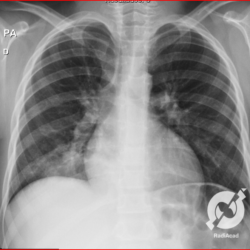

Os agentes etiológicos infecciosos são variados (bactérias, vírus, fungos, parasitas…), mas o que ocorre nos pulmões durante uma infecção por qualquer tipo de agente é a substituição do ar alveolar por secreção (pus, muco, eventualmente sangue ou necrose…) e com isso a manifestação radiográfica vai ser a mesma já que todas estas secreções apresentam a mesma densidade radiográfica: partes moles.

E o nome dado a esta alteração radiográfica que corresponde à substituição do ar alveolar por líquido é a consolidação alveolar.

Uma consolidação alveolar é, por definição, uma opacidade (imagem densa, branquinha) homogênea ou às vezes heterogênea (pela presença de calcificações ou cavidades), de limites mal definidos, exceto quando toca a pleura da parede ou das cissuras pulmonares. É um termo usado tanto em radiografia, como em tomografia computadorizada. Na tomografia, um outro termo é usado: vidro fosco, que é uma opacidade (branquinha mas não tanto como a consolidação), que borra o pulmão mas deixa ver os vasos de permeio (igual bigode de adolescente: dá pra ver todo o fundo).

Nós vamos mostrar aqui um pequeno apanhado de pneumonias de variados agentes, em diversos segmentos e lobos pulmonares, com extensões variadas. O objetivo é identificar o padrão radiológico de consolidação alveolar e não determinar o agente infeccioso, isso vai ser assunto para mais adiante. Aliás já antecipo que é fundamental saber localizar a lesão, porque alguns destes bichos gostam de determinados segmentos, alguns tumores também têm as suas preferências, então localização é fundamental. Se localização não fosse importante, um apartamento na beira do mar sairia o mesmo preço de um apartamento de frente pra BR-101, concordam?

Seguem alguns dos nossos casos de pneumonia para vocês treinarem os olhos e não se apavorarem nos plantões.